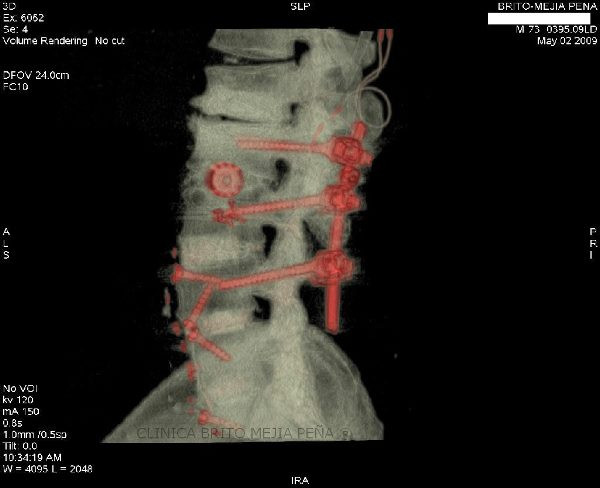

Instrumentalización columna 3D

Instrumentalización columna ósea